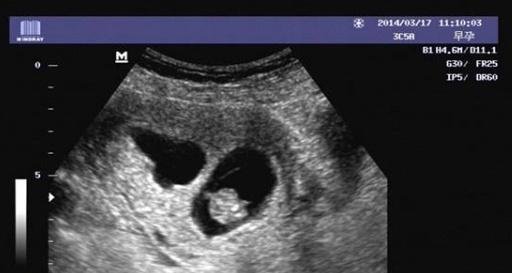

1胎囊的大小:怀孕6周时胎囊直径约2厘米,孕10周时约5厘米,孕15个月时直径约2厘米,25个月时约5厘米为正常。 2胚囊:(长)23*(宽)17*(厚)16 mm 是女孩。或35*34*28mm也是女孩。或18*16*8mm也是女孩。33*18mm是男孩,44*mm是男孩。 350D的BC数据:胎囊29*19 mm是男孩。32*mm是女孩。孕囊35*27mm是女孩。 48W的BC 懷孕胎囊的轉變 1、4周, 胎寶寶僅有2mm。 精卵結合剛進行胚胎著床, 羊膜腔才產生, 容積不大。 超聲波還看不清楚懷孕征兆。 2、5周, 胎寶寶長到4mm, 進入了試管胚胎期, 羊膜腔擴張, 初始心腦血管病出現, 可有心搏。 B超可看到小孕囊, 孕囊約占宮腔內不上1/4, 或由此可見胎

4周胎囊-孕囊 4周 02cm 5周 04cm B超孕囊占宫腔不到1/4 6周 085cm B超胎囊清晰可见 7周 133cm 胎囊约占宫腔的l/3 8周 166cm B超可见胎囊约占官腔1/2 9周 215cm B超可见胎囊几乎占满宫腔 10周 2cm 超可见胎囊开始消失 11周 362cm B超可见胎囊完全消失 一般孕周和孕囊大小不用孕妈妈本人进行纠结比较 胎芽一般是在怀孕三十多天以后开始慢慢形成的,通常妊娠三周至妊娠第一个月称为胎芽期,一般孕6—7周B超可见胎芽,大小在051cm左右,胎芽和孕囊大小的对照关系如下: 怀孕周数 孕囊大小 胎芽 4周 孕囊03cm 孕囊体积很小,超声还看不清妊娠迹象 5周

怀孕4周时,受精卵才着床成功; 怀孕5周时,受精卵着床成功后一边快速进行细胞分裂,一边向四周扩展,而这些细胞将会形成羊膜和血管包裹住 卵黄囊,胎儿就是从卵黄囊开始发育的。 在卵黄囊的外面是孕囊,孕囊是原始的胎盘组织。 所以, 一般在怀孕56周,可以做B超看到孕囊和卵黄囊,月经规律的女性,最早在怀孕35天时可以通过阴超看到孕囊; 怀孕67周时,可以通过B超看到胎3 怀孕5周孕囊大小多少是正常的 1、4周:胎儿只有02厘米。 受精卵刚完成着床,羊膜腔才形成,体积很小。 超声还看不清妊娠迹象。 2、5周:胎儿长到04厘米,进入了胚胎期,羊膜腔扩大,原始心血管出现,可有搏动。 B超可看见小胎囊,胎囊约占宫腔不到1胎芽特征 怀孕的第一个月为胎芽期,新生命在此期的成长速度是其一生中最快的。 妊娠第二周末精卵结合,受精后约4天,分裂成细胞团的精卵沿着 输卵管 到达子宫。 第三周,细胞团脱去外膜,为着床作准备。 第四周,胚泡已牢固地植入子宫里。 在这个